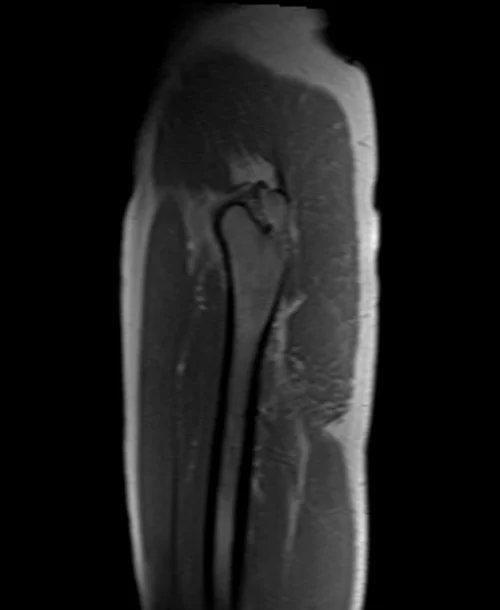

mri hipa localizer 3 - MRI